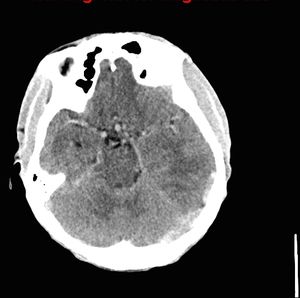

33-year-old male with history of cyanotic congenital heart disease status post multiple palliative cardiac surgeries.